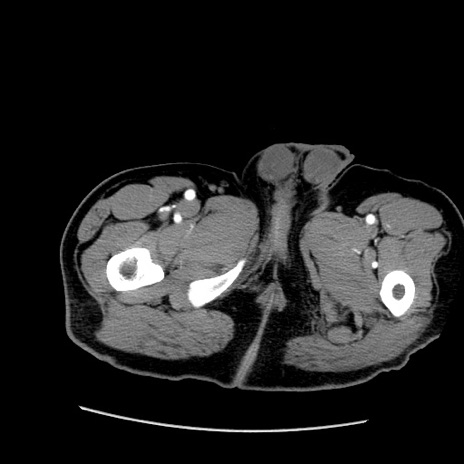

症例22(横断像)

【症例】50歳代男性

【主訴】腹痛

【現病歴】AVMからの被殻出血のため回復期リハ病棟入院中。 本日午後3時頃急に下腹部痛が出現した。

【既往歴】AVM、被殻出血、虫垂炎、高血圧

【身体所見】意識晴明、左半身不全麻痺、会話の理解は良好、36.5°C、腹部:膨隆、全体に板状硬、下腹部正中に圧痛点あり、反跳痛-、筋性防御不明、右下腹部にope scar

【データ】WBC 9400、CRP 0.06